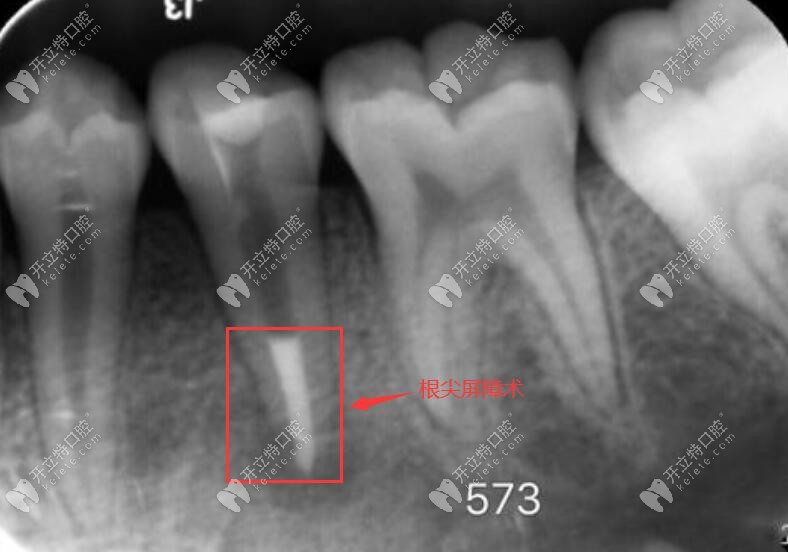

這兩者主要用于根尖屏障術(shù)和蓋髓術(shù),也就說在顧客的有根尖炎癥、根尖孔未閉合、牙髓壞死、伴有跟根尖周炎、根尖未發(fā)育完全的狀態(tài)下的一個修補(bǔ),都可以使用的根尖屏障術(shù)進(jìn)行治療。

如圖,根尖屏障術(shù):通俗的講就是把已經(jīng)有炎癥的牙髓去掉,并使用mta或者iroot材料,把根尖位置堵住,將牙周膜和牙髓隔離開。

mta在根尖屏障術(shù)里的應(yīng)用